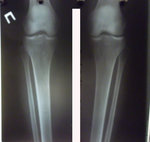

Исходник - 35 лет.

Укорочение правой ноги - 2 см.

Левая голень более деформирована.

Диагноз: Укорочение правой ноги - 2 см.